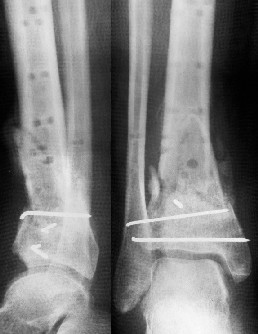

Операции: 1 Клиновидная резекция на вершине деформации м\берцовой кости.

2 Тугоподвижный ложный сустав н\3 б\берцовой кости. Рубцы выполняющие пространство между отломками, канал проксимального отломка иссечены.

Одномоментное устранение деформации, остеосинтез Г-образной пластиной.

Пластика по Хахутову.

Заживление проксимальной части раны вторичным натяжением без нагноения. Рана зажила. Спицы удалены через 1,5 недели после операции.

Фиксация

в гипсе